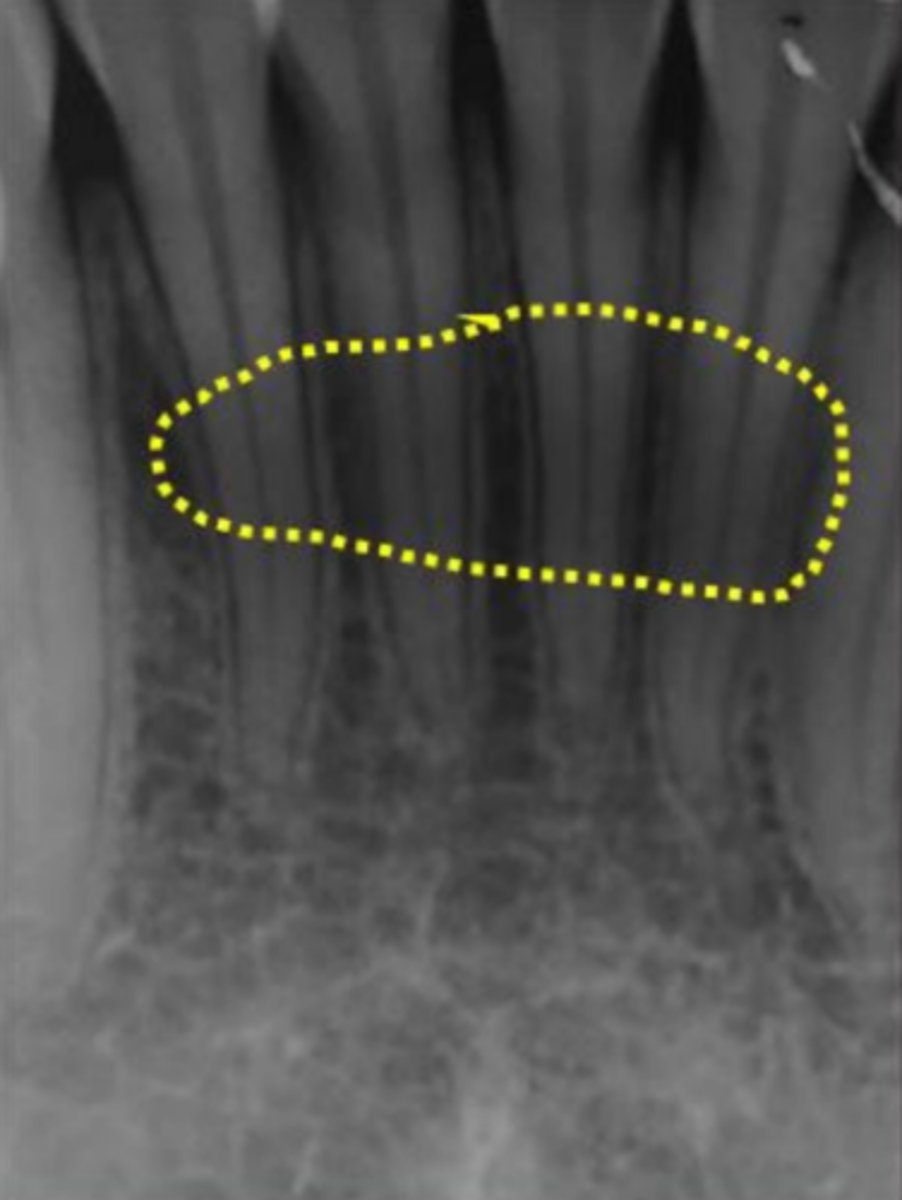

57

New cards

Mandibular canal

What is causing the thick radiolucent line surrounding the dotted line?

<p>What is causing the thick radiolucent line surrounding the dotted line?</p>